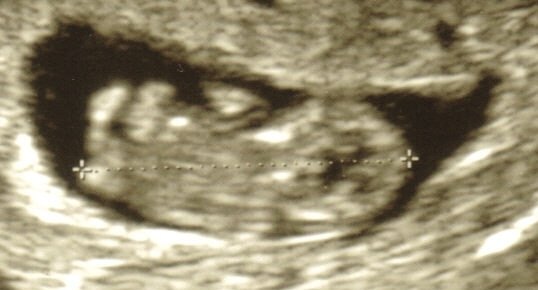

Billed 1: terminsscanning 6+5 (hjerteblink)

Det jeg så ved terminsscanning var ikke et blink som forventet, men mere at man kunne se en muskel, der arbejdede. Altså det ligner et bankende hjerte og ikke som et lysblink...hi hi, ved ikke hvorfor jeg havde en forestilling om, at det var et rigtig blink (nu kan du se det, nu kan du ikke)